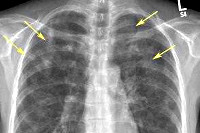

При инструментальном исследовании может сложиться впечатление пневмонии: хрипы в легких, наличие очагов инфильтрации на рентгенограмме грудной клетки.

При рентгенологическом исследовании легких отмечается наличие округлых, овальных, звездчатых, фестончатых, многоугольных инфильтратов. Инфильтраты могут быть как одиночными, так и множественными, обнаруживаются в одной доле или по всему легкому. Контуры их неровные, расплывчатые. При наличии сопутствующего ателектаза они становятся ровными. Эозинофильные инфильтраты выявляются в пределах 2-3 недель; у отдельных больных, исчезнув, они появляются вновь спустя некоторое время, сохраняясь месяцами.

В миграционной стадии основывается на распознавании эозинофильных инфильтратов с учетом клинико- рентгенологических, гематологических и иммунологических данных. Рентгенологическая картина этих инфильтратов может симулировать туберкулез, пневмонию, опухоль легкого. Основное отличие инфильтратов при аскаридозе быстрое их исчезновение без каких-либо остаточных явлений. Подобные инфильтраты могут обнаруживаться и при других гсльм и птозах анкилостомидозах и стронгилоидозе.